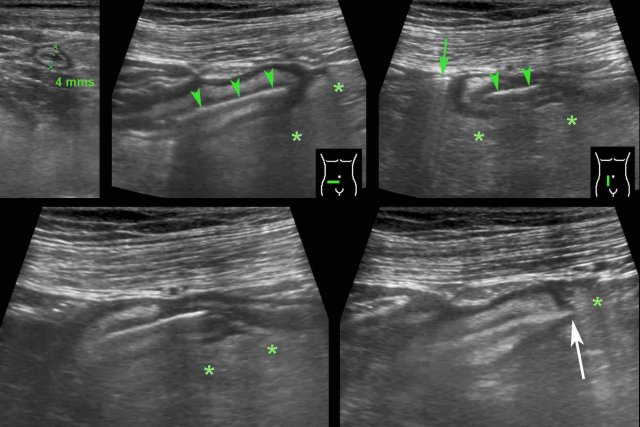

This 48 year old woman was submitted with severe periumbilical pain since 12 hours (Lab: 15 leukocytes, CRP 7).

The next day the pain subsided, but the CRP went up to 65.

US of the periumbilical area, showed edematous wall thickening of small bowel (b.) with normal peristalsis.

There was a tiny fluid collection (f.) and inflammation of the  hyperechoic and non-compressible mesentery (*).

Subsequent CT confirmed small bowel wall thickening (b.) and fat stranding (*) in the mesentery. In the left paracolic gutter, a fishbone (arrow) was found.

Apparently the fishbone, after perforating the jejunum, did migrate to that spot.

Subsequent laparoscopical exploration was unable to identify the fishbone.

She made an uneventful recovery with antibiotics.

CT scan, performed for other reasons 18 months later, showed slight migration of the fish bone, apparently well-encapsulated.

Patient is still doing well eight years later.